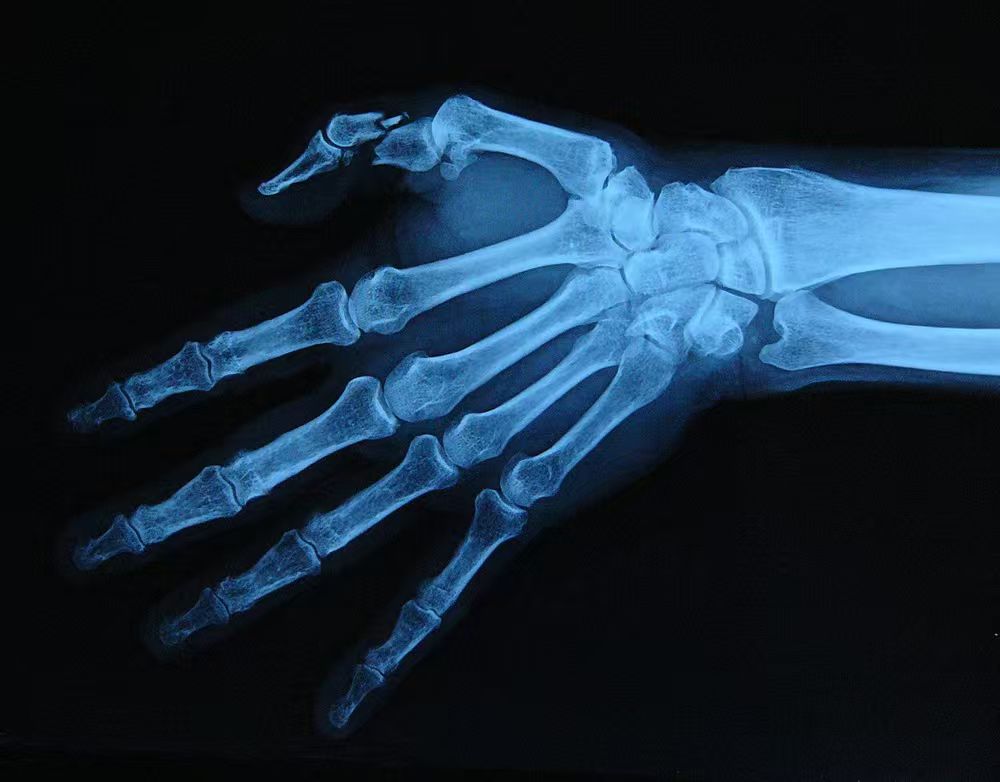

人类的手部由27块骨头组成。在竞技体育中,最容易发生骨折的部位通常集中在掌骨(Metacarpals)和舟状骨(Scaphoid)。